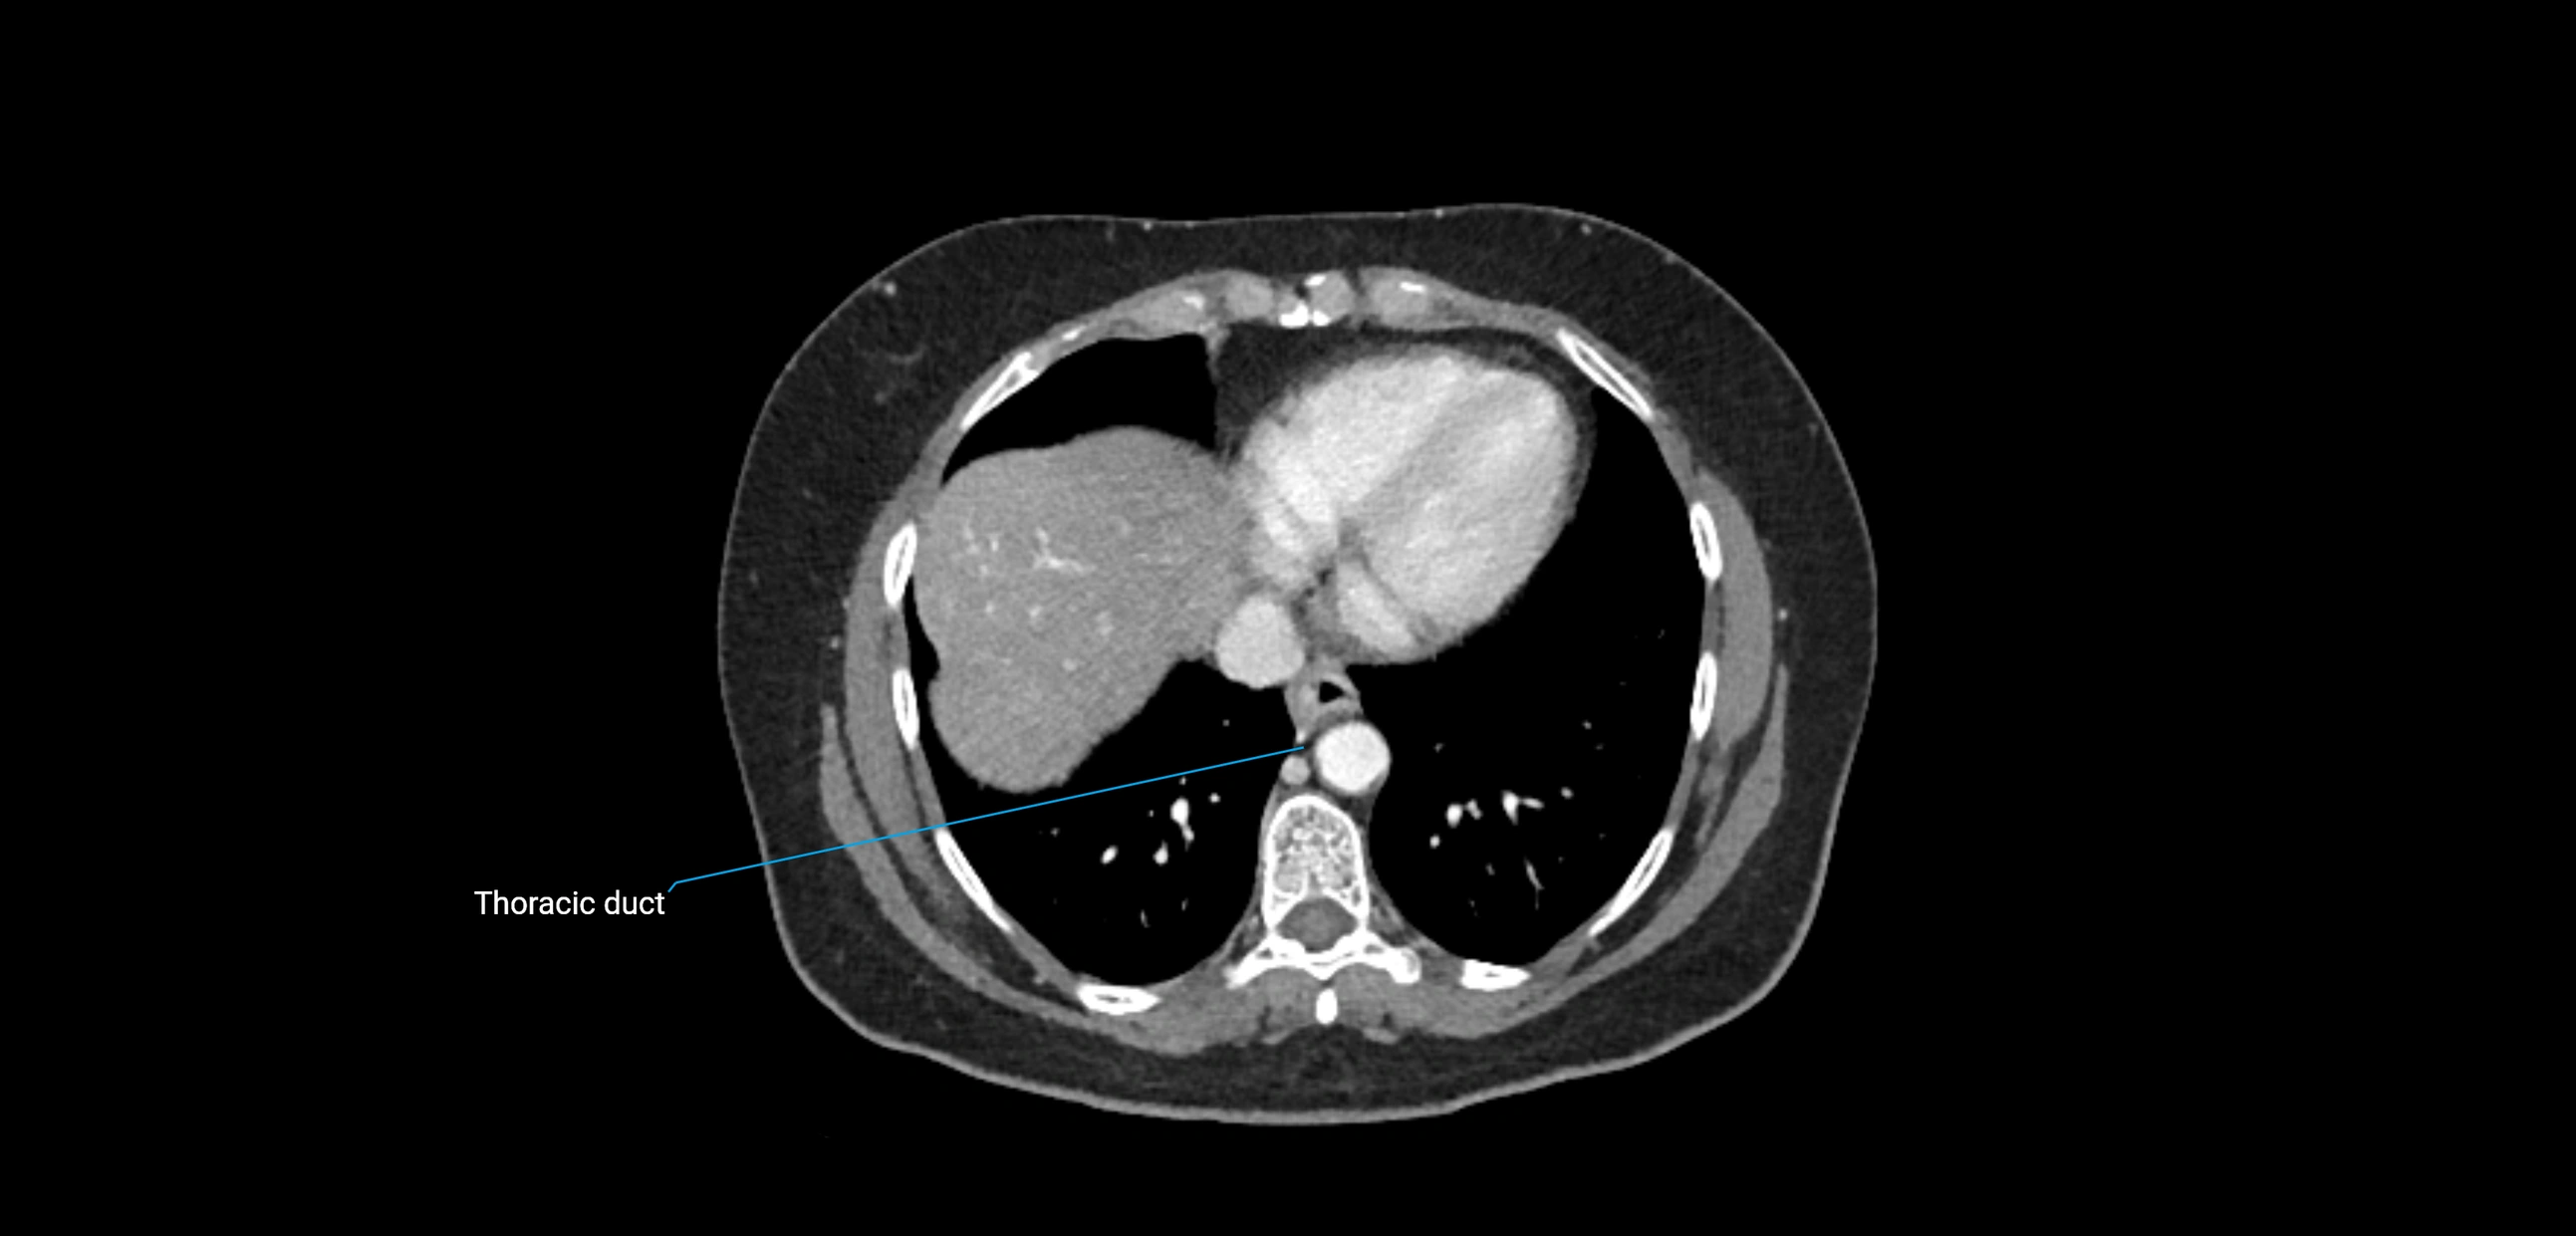

These nodes receive lymph from a wide range of abdominal and pelvic structures. Specifically, they drain lymph from the kidneys, suprarenal glands, gonads (testes/ovaries), uterus, uterine tubes, and pelvic organs, before converging into the lumbar lymphatic trunks, which terminate in the cisterna chyli → thoracic duct.

• Provide a major pathway to the cisterna chyli and thoracic duct